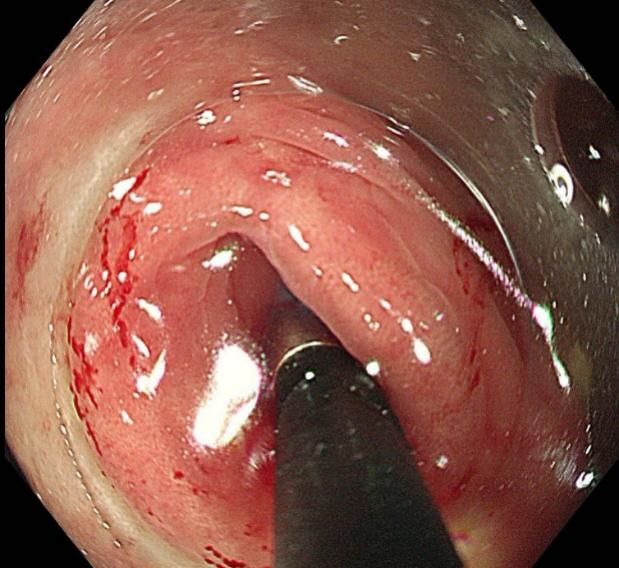

手术全程在高清内镜直视下进行,先将肠镜送至回盲部,定位阑尾开口后,小心翼翼地将子镜置入阑尾腔内。在高清内镜直视下,隐藏在阑尾里的粪石清晰可见。医护人员默契配合,利用专用取石器械,稳稳抓住粪石并缓缓取出。整个手术过程顺利,耗时短,创伤极小,患者全程不适。